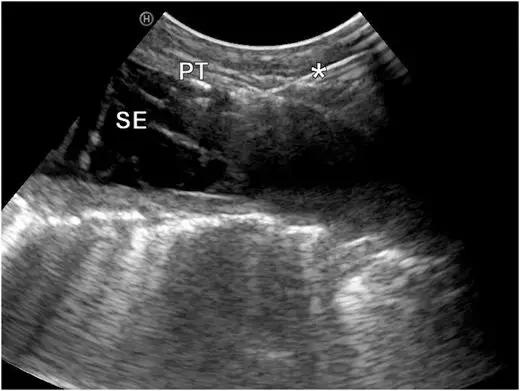

三、彩超引导下胸膜活检

超声指引下,切割活检针达到目标部位后扣动弹簧扳机完成活检,所以特异性和敏感性都不错。

这是在彩超引导下的胸膜活检,胸水较少,胸膜局灶增厚。在穿刺中,可以看到针的所在位置。